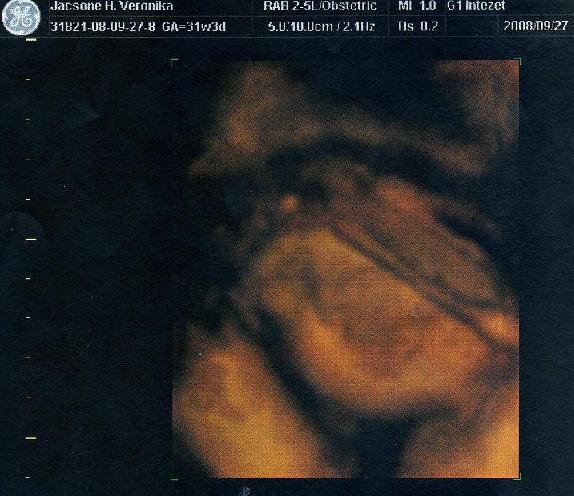

Gratula Izácskához, nagyon szépen látszik a lényeg!!!!